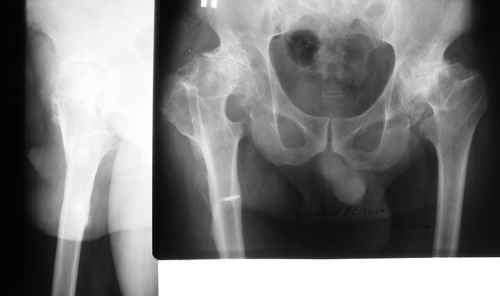

пациент 60 лет.В 1980 году медиализирующая остеотомия правого бедра с

фиксацией пластиной Петуховой.

В 2006 году произведено удаление пластины. В настоящий момент планируется

эндопротезирование правого тазобедренного сустава. В наличии эндопротезы

De-Puy, Corail, AML, Biomet, ножка Taperloc.

Возможные варианты установки ножки:

1)установить ножку в основание диафиза

2)установить ножку в вальгусном положении

3)выполнить поперечную остеотомию бедра на уровне смещения с

последующим остеосинтезом ножкой эндопротеза. Прощу вас высказать

свое мнение